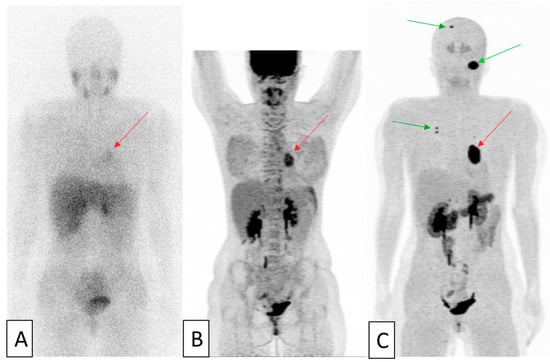

- Gebhart, G.; Lamberts, L.E.; Wimana, Z.; Garcia, C.; Emonts, P.; Ameye, L.; Stroobants, S.; Huizing, M.; Aftimos, P.; Tol, J.; et al. Molecular imaging as a tool to investigate heterogeneity of advanced HER2-positive breast cancer and to predict patient outcome under trastuzumab emtansine (T-DM1): The ZEPHIR trial. Ann. Oncol. 2016, 27, 619–624. [Google Scholar] [CrossRef] [PubMed]

- Clark, A.S.; DeMichele, A.; Mankoff, D. HER2 imaging in the ZEPHIR study. Ann. Oncol. 2016, 27, 555–557. [Google Scholar] [CrossRef] [PubMed]